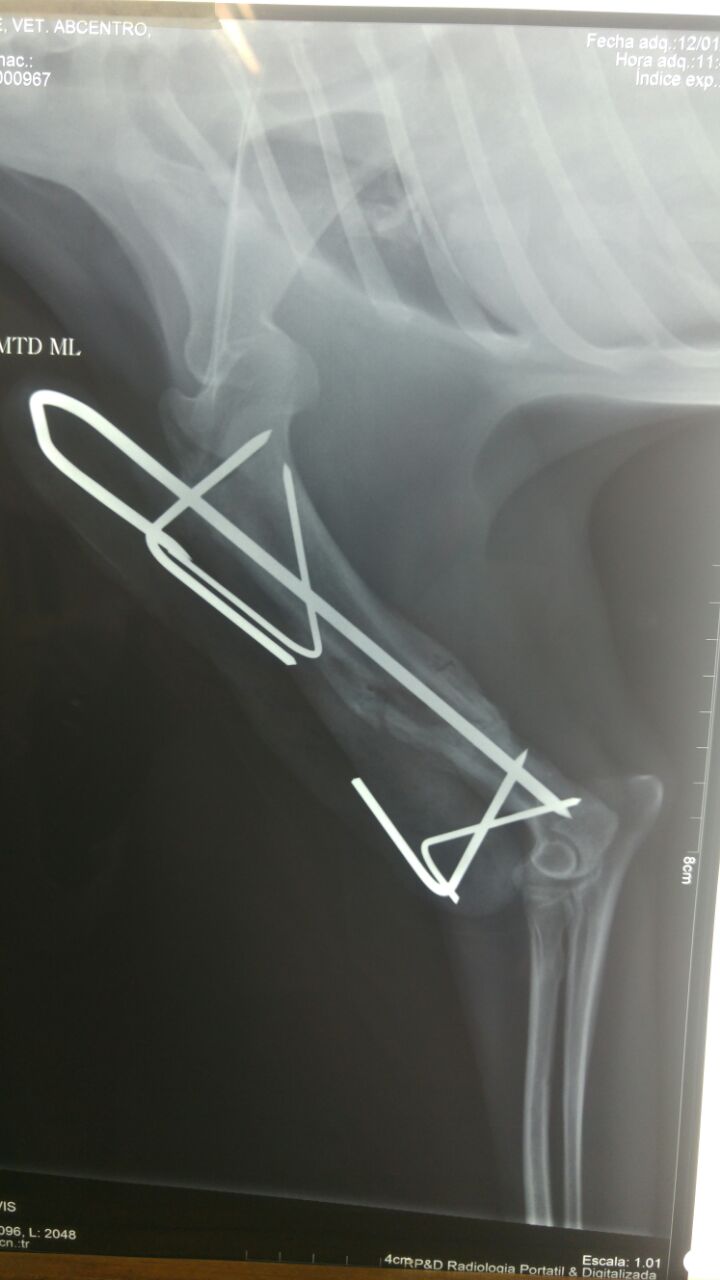

- Cirugía ortopédica